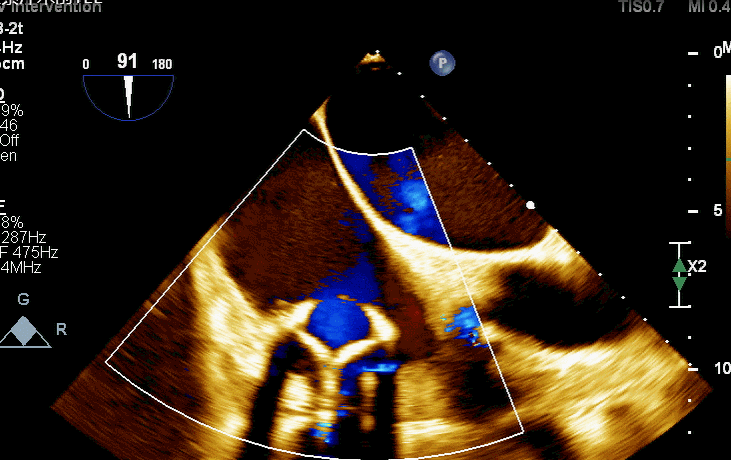

食道超声评估

术后TV生物瓣活动良好

术后三维超声同时显示MV机械瓣及新的TV生物瓣